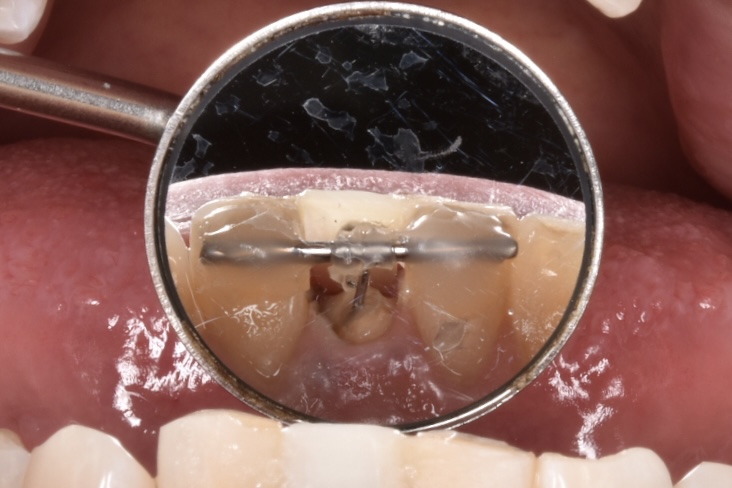

こちらが初診時のレントゲン写真です。歯が水平的に破折していて歯の一部が骨のトップに差し掛かっていることがわかります。

写真の青字:骨のライン

写真ピンク字:歯の断端